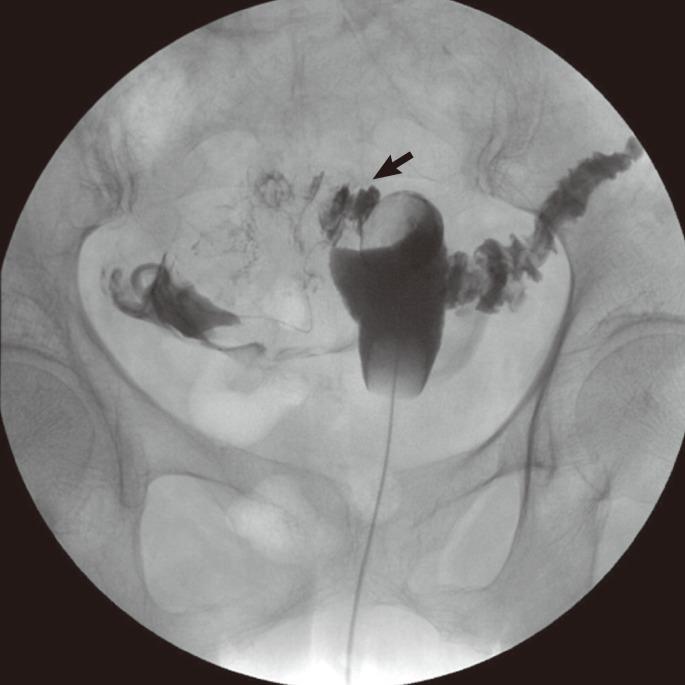

Colouterine fistula is an extremely rare condition because the uterus is a thick, muscular organ. Here, we present a case of a colouterine fistula secondary to colonic diverticulitis. An 81-year-old woman was referred to the emergency department with abdominal pain and vaginal discharge. Computed tomography showed a myometrial abscess cavity in the uterus adherent to the thick sigmoid wall. Upon contrast injection via the cervical os for fistulography, we observed spillage of the contrast into the sigmoid colon via the uterine fundus. Inflammatory adhesion of the distal sigmoid colon to the posterior wall of the uterus was found during surgery. The colon was dissected off the uterus. Resection of the sigmoid colon, primary anastomosis, and repair of the fistula tract of the uterus were performed. The postoperative course was uneventful. This case represents an unusual type of diverticulitis complication and illustrates diagnostic procedures and surgical management for a colouterine fistula.

子宫结肠瘘极为罕见,因为子宫是一个厚实的肌肉器官。在此,我们报告一例继发于结肠憩室炎的子宫结肠瘘病例。一名81岁女性因腹痛和阴道分泌物增多被转诊至急诊科。计算机断层扫描显示子宫肌层有一个脓肿腔,与增厚的乙状结肠壁粘连。通过宫颈口注入造影剂进行瘘管造影时,我们观察到造影剂经子宫底部溢入乙状结肠。手术中发现乙状结肠远端与子宫后壁存在炎性粘连。将结肠从子宫上分离。进行了乙状结肠切除、一期吻合以及子宫瘘管修复。术后过程顺利。该病例代表了一种不寻常类型的憩室炎并发症,并说明了子宫结肠瘘的诊断方法和手术治疗。